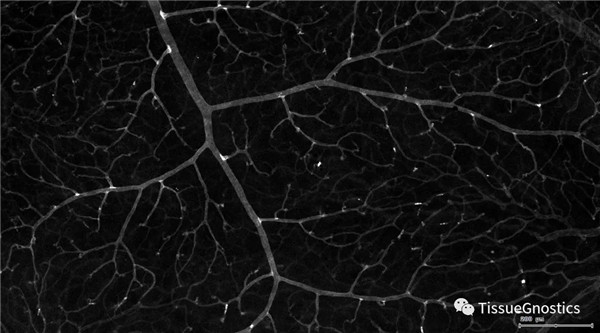

單通道灰階圖(↑:FITC,↓:Texa Red)

血管識別:根據Texa Red通道進行識別,并去除面積小的及非同一焦面的血管,僅對確定的清晰的同一焦面的大血管進行面積統計。